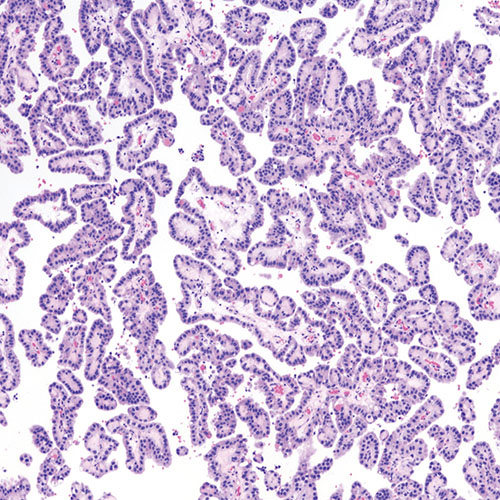

Choroid plexus papillomas form in the choroid plexus, which is the area at the base of the brain where the fluid that cushions and protects the brain is made. They present as finger-like structures and are typically low-grade but can sometimes become aggressive. Even low-grade tumors can be lethal if they block the flow of this fluid, causing excessive pressure in the brain.

Choroid plexus papilloma under a microscope.

Choroid plexus papilloma